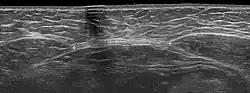

Ультразвуковое исследование может потребоваться в отдельных случаях, например при наличии избыточного веса у пациентки, когда осмотр и пальпация не дают однозначной четкой картины. УЗИ хорошо видит слои передней брюшной стенки и позволяет точно измерить ширину диастаза на разных уровнях.